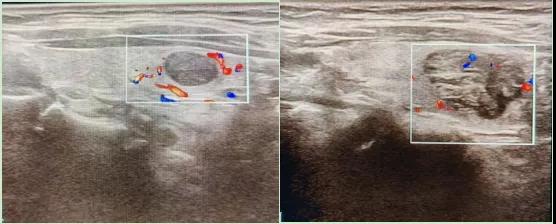

二、彩超如何“揪出”甲狀腺瘤?

彩色血流顯示:用紅藍色標記血流信號,區分腫瘤的供血情況。

1.形態:良性多呈圓形,邊界清晰;惡性可能不規則、邊緣模糊。

4.血流信號:惡性結節常有豐富紊亂的血流。